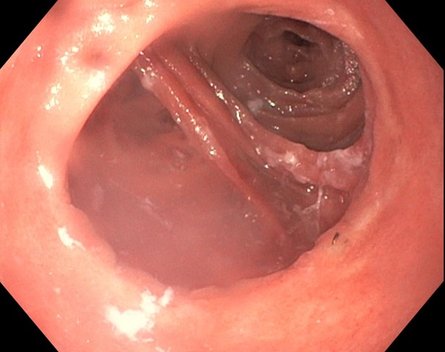

Eine Patientin stellte sich über unser Adipositaszentrum mehrere Jahre nach Magenbypass-Operation mit erneuter Gewichtszunahme und ausgeprägten Dumping-Beschwerden vor. In der Magenspiegelung zeigte sich eine deutlich erweiterte Anastomose.

Bild 1: Weit offene Anastomose vor der Behandlung

Statt einer erneuten Operation kann in vielen Fällen heute ein schonendes endoskopisches Verfahren eingesetzt werden. Dabei erfolgt die Behandlung von innen, also über eine Magenspiegelung – ganz ohne Bauchschnitt. In diesem Fall wurde eine endoskopische Verkleinerung der Anastomose mit dem BARS™-System (Ovesco) durchgeführt. Der Eingriff dauert in der Regel nur kurze Zeit, erfolgt meist in Sedierung und erfordert keinen längeren Krankenhausaufenthalt.

Bild 2: Verkleinerte Anastomose nach endoskopischer Therapie